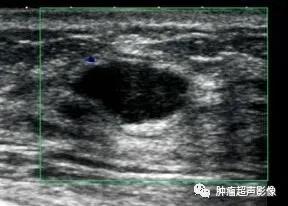

(图片由余杭区第一人民医院超声科陈晓冰医师提供并授权)女62,左乳低回声,边界尚清,内回声欠均,形态欠规则,CDFI:内血流信号不明显。此例由于年龄较大且肿块形态欠规则,容易考虑恶性,但是此肿块边界尚清,周围无高回声晕,后方回声无衰减,呈平行位生长,无血流及腋下淋巴结肿大,这些均提示良性征象。